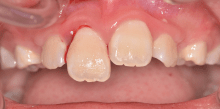

Im Bereich der Zahnheilkunde resultieren Traumata häufig in Verletzungen der Frontzähne. Aber nicht nur die Soforttherapie, auch Spätfolgen von Zahnverletzungen...

Im Bereich der Zahnheilkunde resultieren Traumata häufig in Verletzungen der Frontzähne....

Dislokationsverletzungen treten je nach Richtung und Schwere der Krafteinwirkung in unterschiedlichem Ausmaß und unterschiedlicher Auswirkung auf. Dabei...

Dislokationsverletzungen treten je nach Richtung und Schwere der Krafteinwirkung in unterschiedlichem...

Die Bedeutung der Nachkontrollen und die Notwendigkeit des interdisziplinären Austausches bei der Behandlung von Traumata soll anhand des nachfolgenden...

Die Bedeutung der Nachkontrollen und die Notwendigkeit des interdisziplinären Austausches...